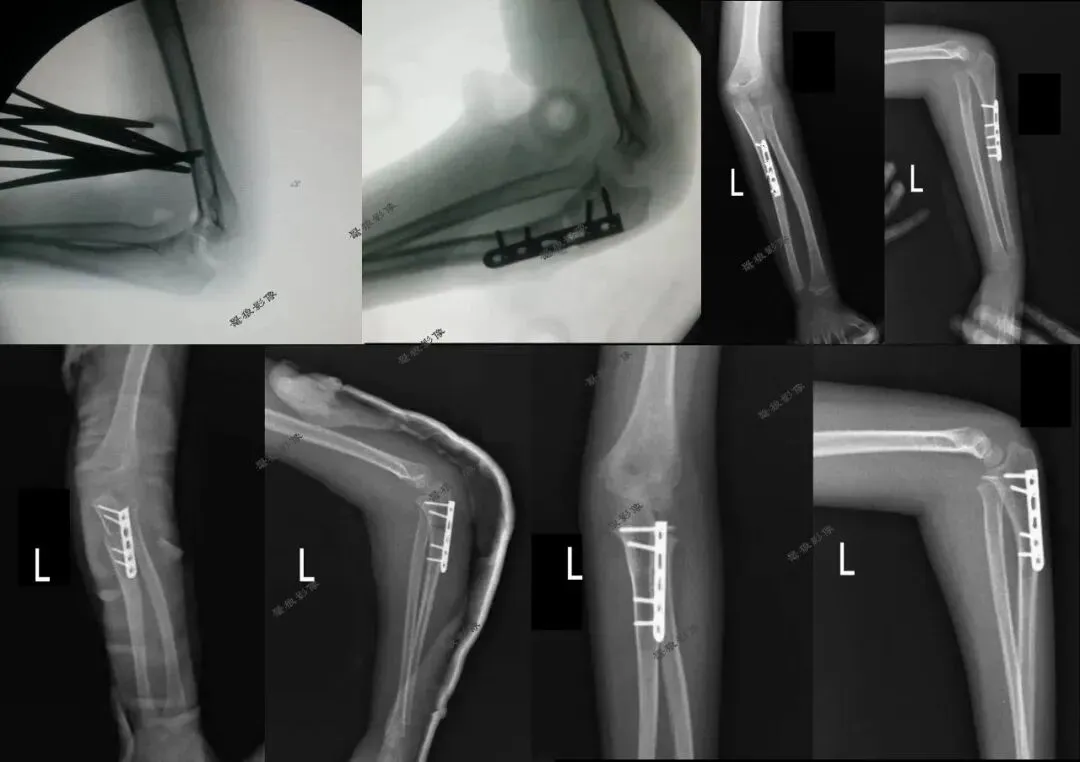

七、需要警惕以下情况发生

三、假如说病人是靠近腕关节那一侧的桡尺骨有问题时,我们拍摄桡尺骨正侧位也只包括一侧腕关节时,这样的拍摄方法(全部伸直或者全部弯曲)也许不会发现此问题。但是病人是肘关节那一侧的桡尺骨有问题时,我们拍摄桡尺骨必须要包括肘关节时,这样的拍摄方法(全部伸直或者全部弯曲)就有问题啦!桡尺骨侧位片伸直显示不出肘关节侧位,桡尺骨正位片弯曲90°显示不出肘关节正位,我们都没法查看肘关节的解剖细节!

3.在一些特殊检查时,可能会出现影像技术的最终目标与技术标准发生冲突或不能兼容的情况。这时,应当视患者实际情况向标准靠近,但是却不能掩盖患者的伤情、病情和畸形状态,不能违背影像检查的最终目标。

4.对一些特殊病人、特殊体位处理的基本理念,在实际工作中应酌情考量而为......